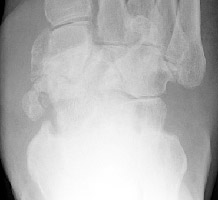

Gout: Large erosions 5th MTP joint

++